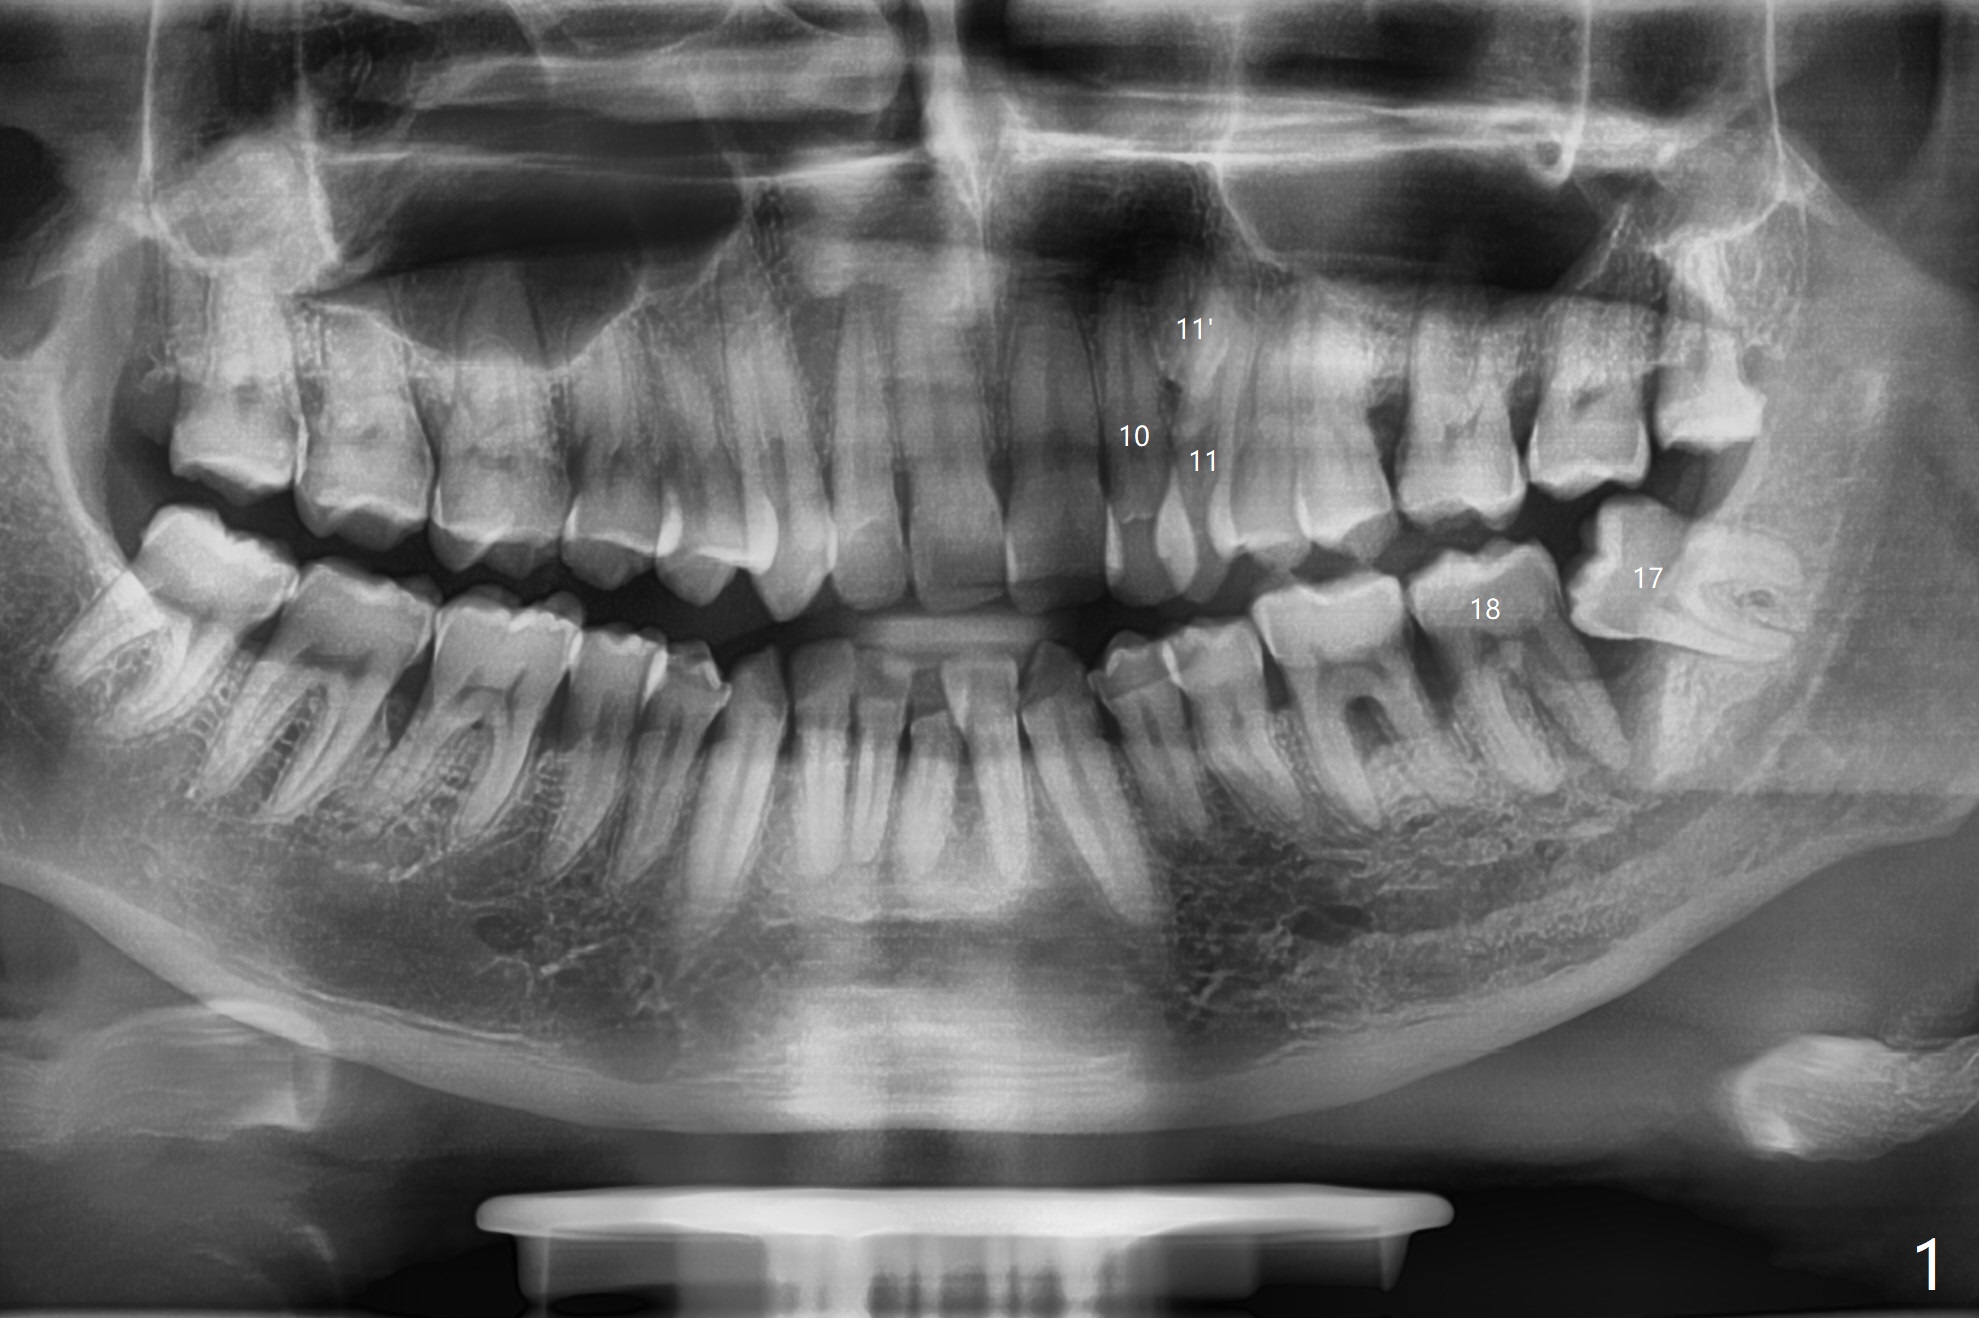

A 43-year-old man requests #17 extraction (Fig.1,2); the tooth #18 has large periapical radiolucency at the distal root. After SRP and extraction, Osteogen plug is placed in #17 sockets (Fig.3 P), while Vanilla Cancellous/Cortical Mix (allograft) 18 distal (*). The wound is closed with 4-0 plain gut suture. Similar to his son, he has crowding with #10 cross bite, #11 labioversion and a possible supernumerary tooth (11'). Seven months postop, not only does the periradicular radiolucency decrease around the distal root of the tooth #18 (Fig.4 *), but also the mesial and distal sockets of the 3rd molar heal (M, D). The patient is concerned about the sensitivity of the tooth #18, which is stable with the healthy gingiva. The sensitivity disappears 1 year postop, but there is a ~ 10 mm pocket distal of #18. Endo ice test shows necrosis. Endodontic referral is recommended. If endodontic treatment is not practical, periodontal referral is next step with laser modality.